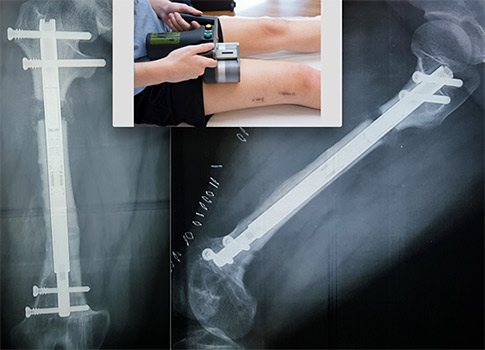

Μικρή ασθενής που πάσχει από αχονδροπλασία με ανισοσκελία και διαταραχή του μηχανικού άξονα των δύο κάτω άκρων, υποβλήθηκε σε αμφοτερόπλευρη τοποθέτηση ηλεκτρομαγνητικά κατευθυνόμενων ήλων, τεχνολογίας αιχμής, με σκοπό την έναρξη της επιμήκυνσης των μηριαίων (έως 6 εκ αρχικά), την αποκατάσταση της ανισοσκελίας (2,5 εκ) και την οξεία διόρθωση του μηχανικού άξονα.

Η πολύωρη επέμβαση είχε άριστο αποτέλεσμα, ελάχιστη ενόχληση για την ασθενή και μόλις διήμερη νοσηλεία.

Η πορεία της επιμήκυνσης εξελίσσεται ομαλά, ενώ περπατά με άνεση.